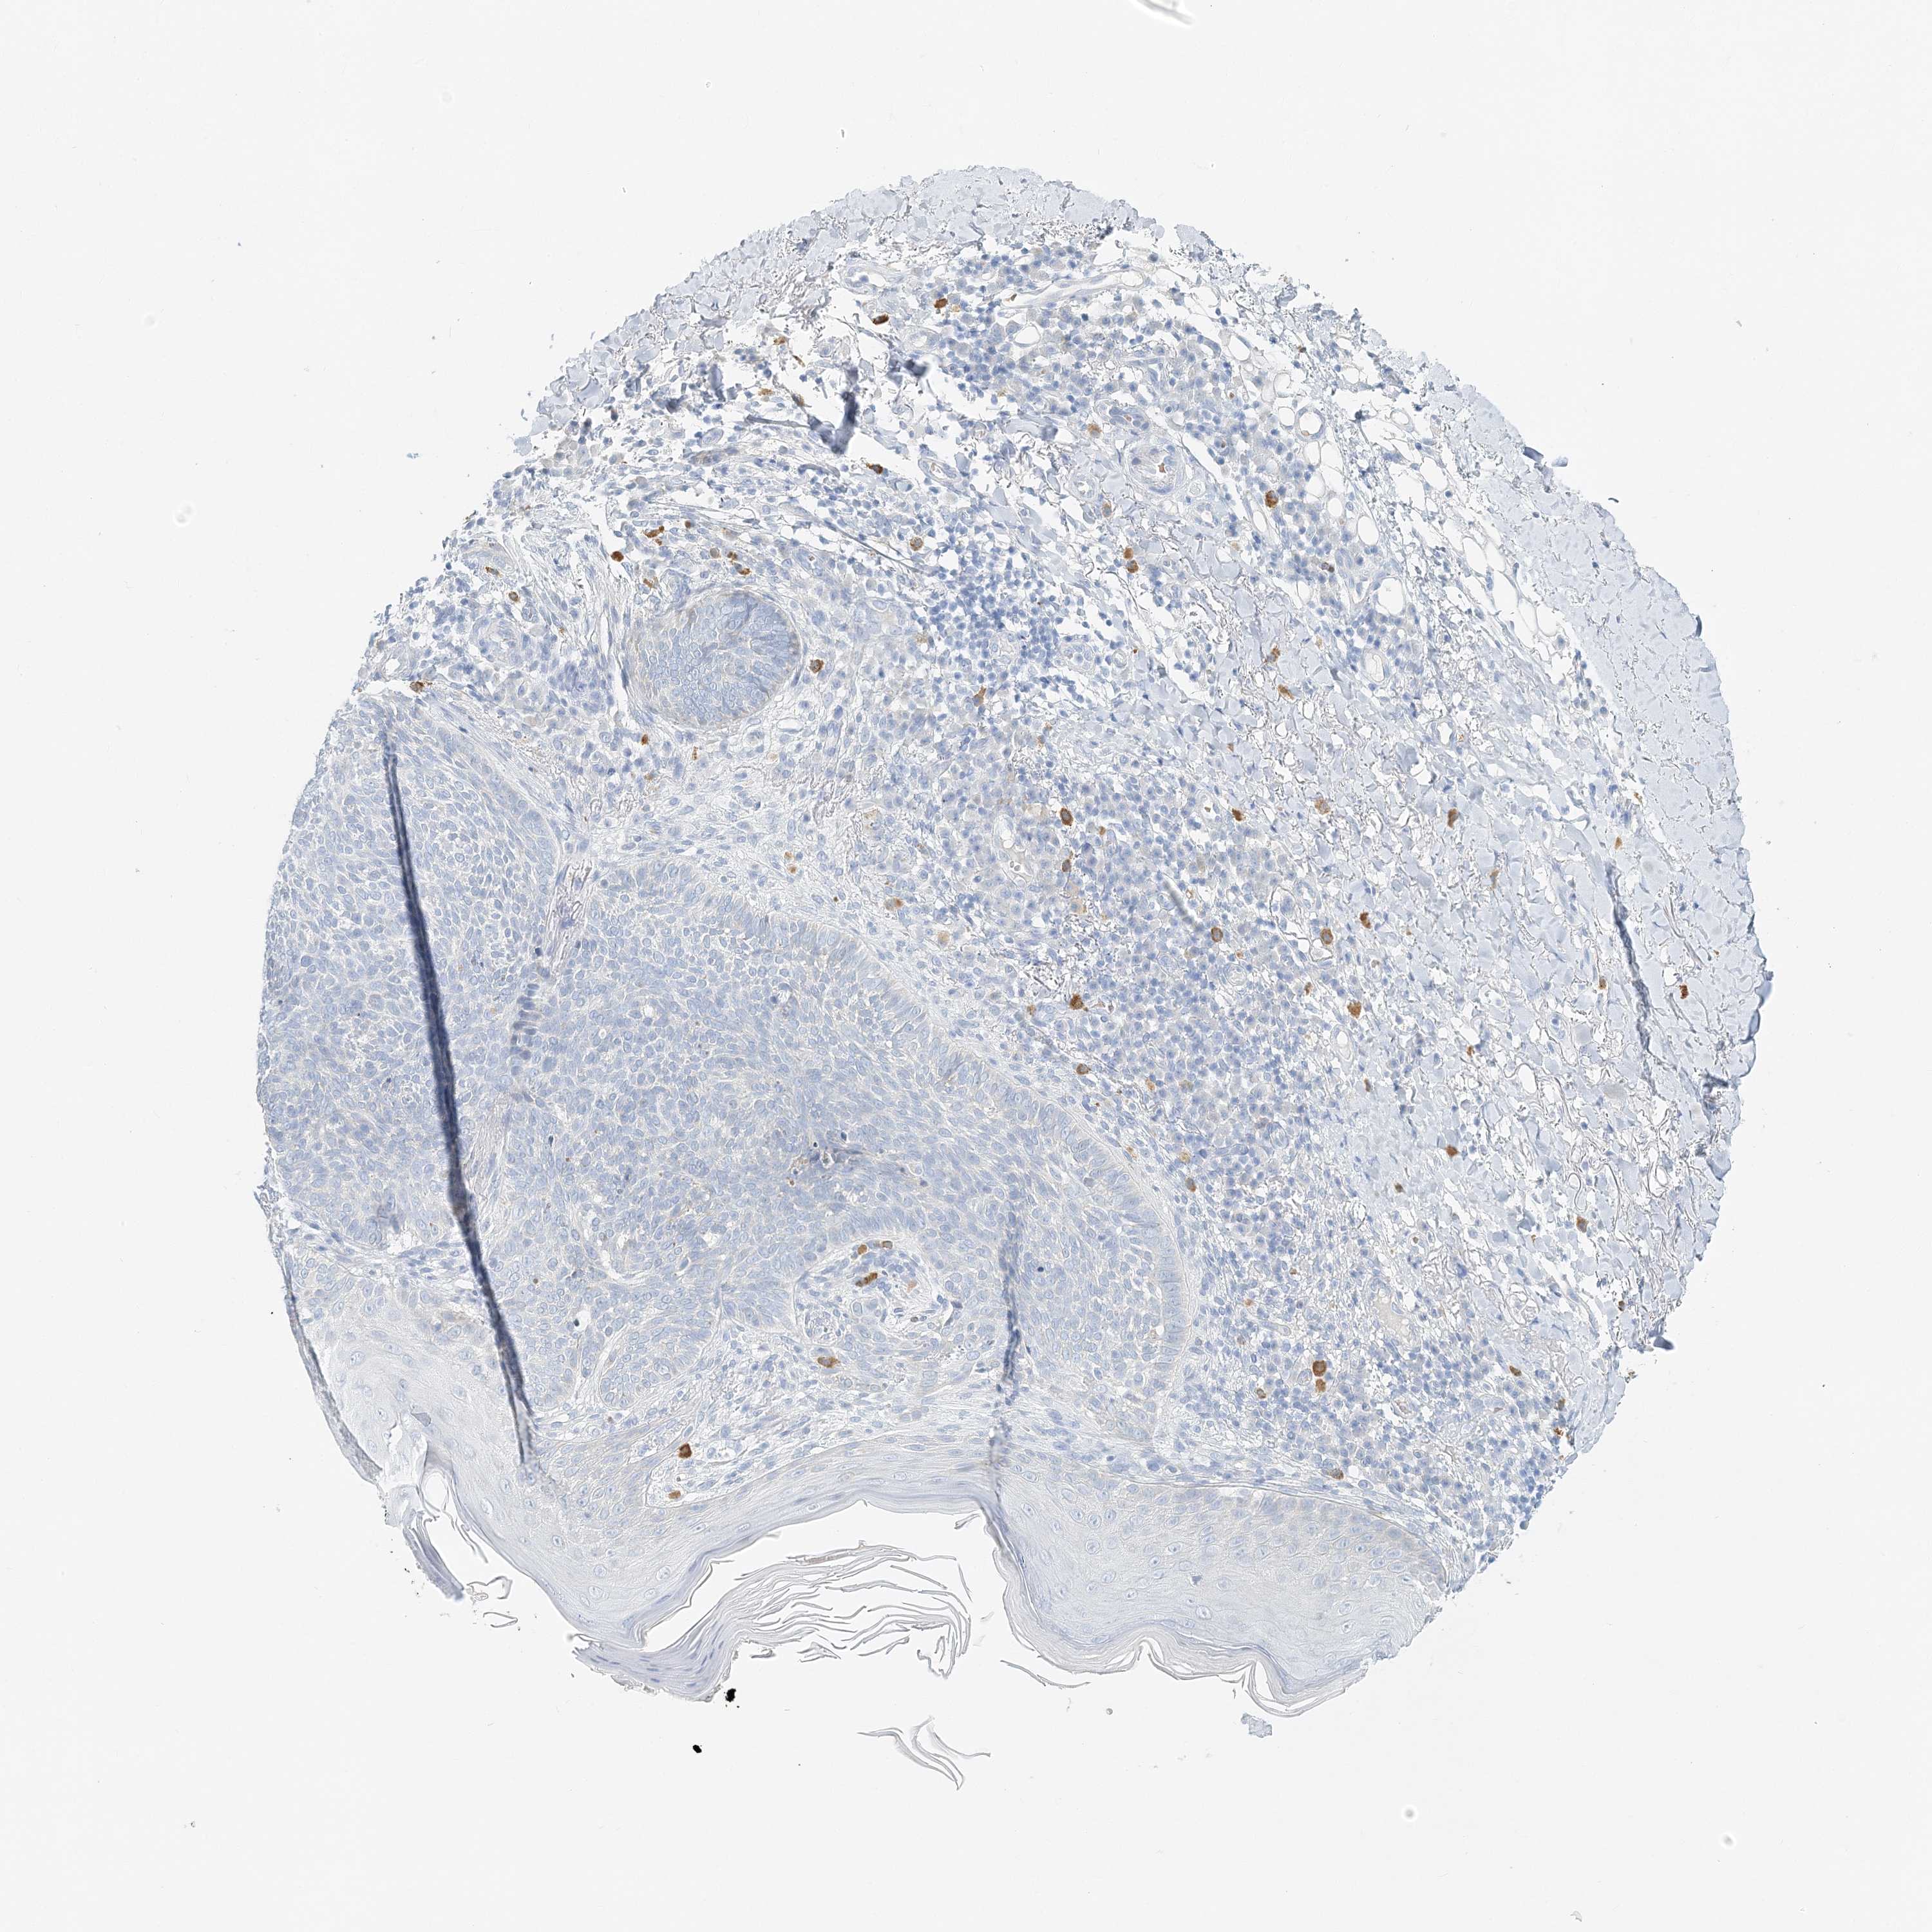

Basal cell and squamous cell cancer

SKIN CANCER - Protein expressioni

A mouse-over function shows sample information and annotation data. Click on an image to view it in a full screen mode. Samples can be filtered based on level of antibody staining by selecting one or several of the following categories: high, medium, low and not detected. The assay and annotation is described here.

Antibody stainingi

Antibody staining in the annotated cell types in the current human tissue is reported as not detected, low, medium, or high, based on conventional immunohistochemistry profiling in selected tissues. This score is based on the combination of the staining intensity and fraction of stained cells.

Each image is clickable and will lead to virtual microscopy that enables deeper exploration of all samples and also displays staining intensity scores, fraction scores and subcellular localization as well as patient and tissue information for each sample.

Antibody HPA035675

Squamous cell carcinoma, NOS